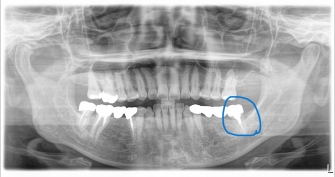

◎右写真 移植後 10年経過のレントゲン写真

右上の親知らずを、左下の第二大臼歯(歯牙破折のため抜歯になったため)に移植する外科処置を行いました。